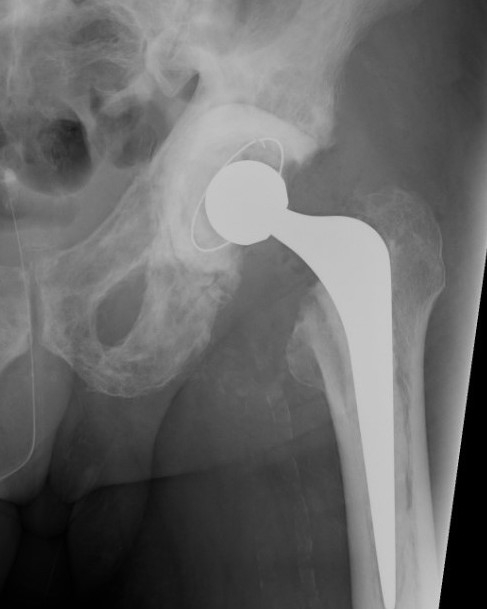

THA

Technical issues

Bleeding

- preoperative calcitonin / bisphosphonates / EPO / Iron

- intra-operative blood salvage system

Acetabulum

- difficult reaming due to hard bone

- protrusio - consider medial bone graft / cages / lateral offset liners

- limited ability for cement interdigitation - uncemented cups may be preferrred

Femur

- coxa vara - risk varus femoral implants

- difficulty broaching femur - may need burrs

- femoral bowing - may need osteotomy

- poor cement interdigitation - uncemented stems may be preferred

- brittle bone - increased risk fracture

Heterotopic ossification

- high risk

Progression of disease and loosening of cemented acetabular component

Results

Martino et al J Orthop Traumatol 2021

- 66 registry patients with Paget's undergoing THA: 10 year survival 90%

- 29 institution THA

- 50% HO, 14% varus stems, high transfusion rates

- systematic review of THA and TKA in Pagets

- 19 articles and 10,000 patients

- mortality 30% at 8 years

- revision rate 4% at 7 years